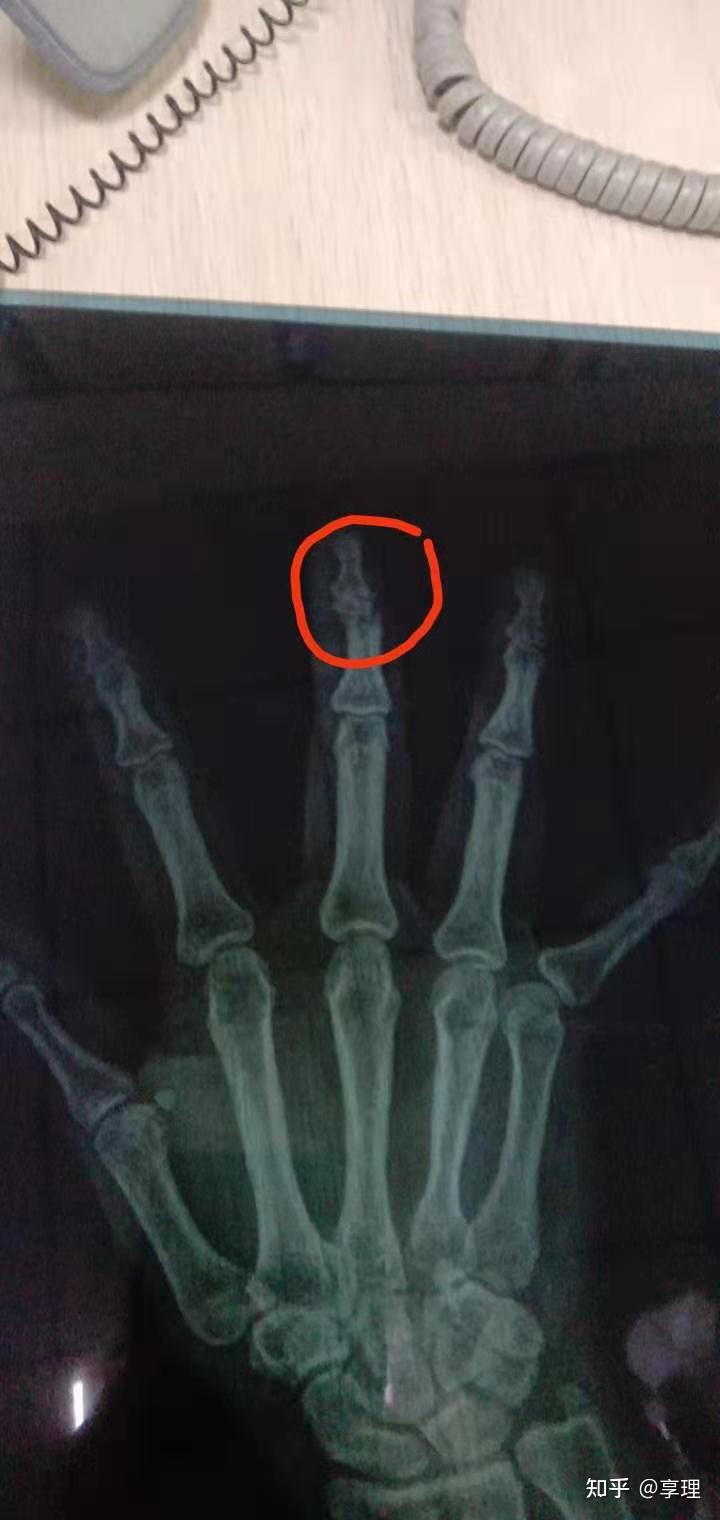

手指指关节骨折工伤评几级

图片尺寸1080x1441